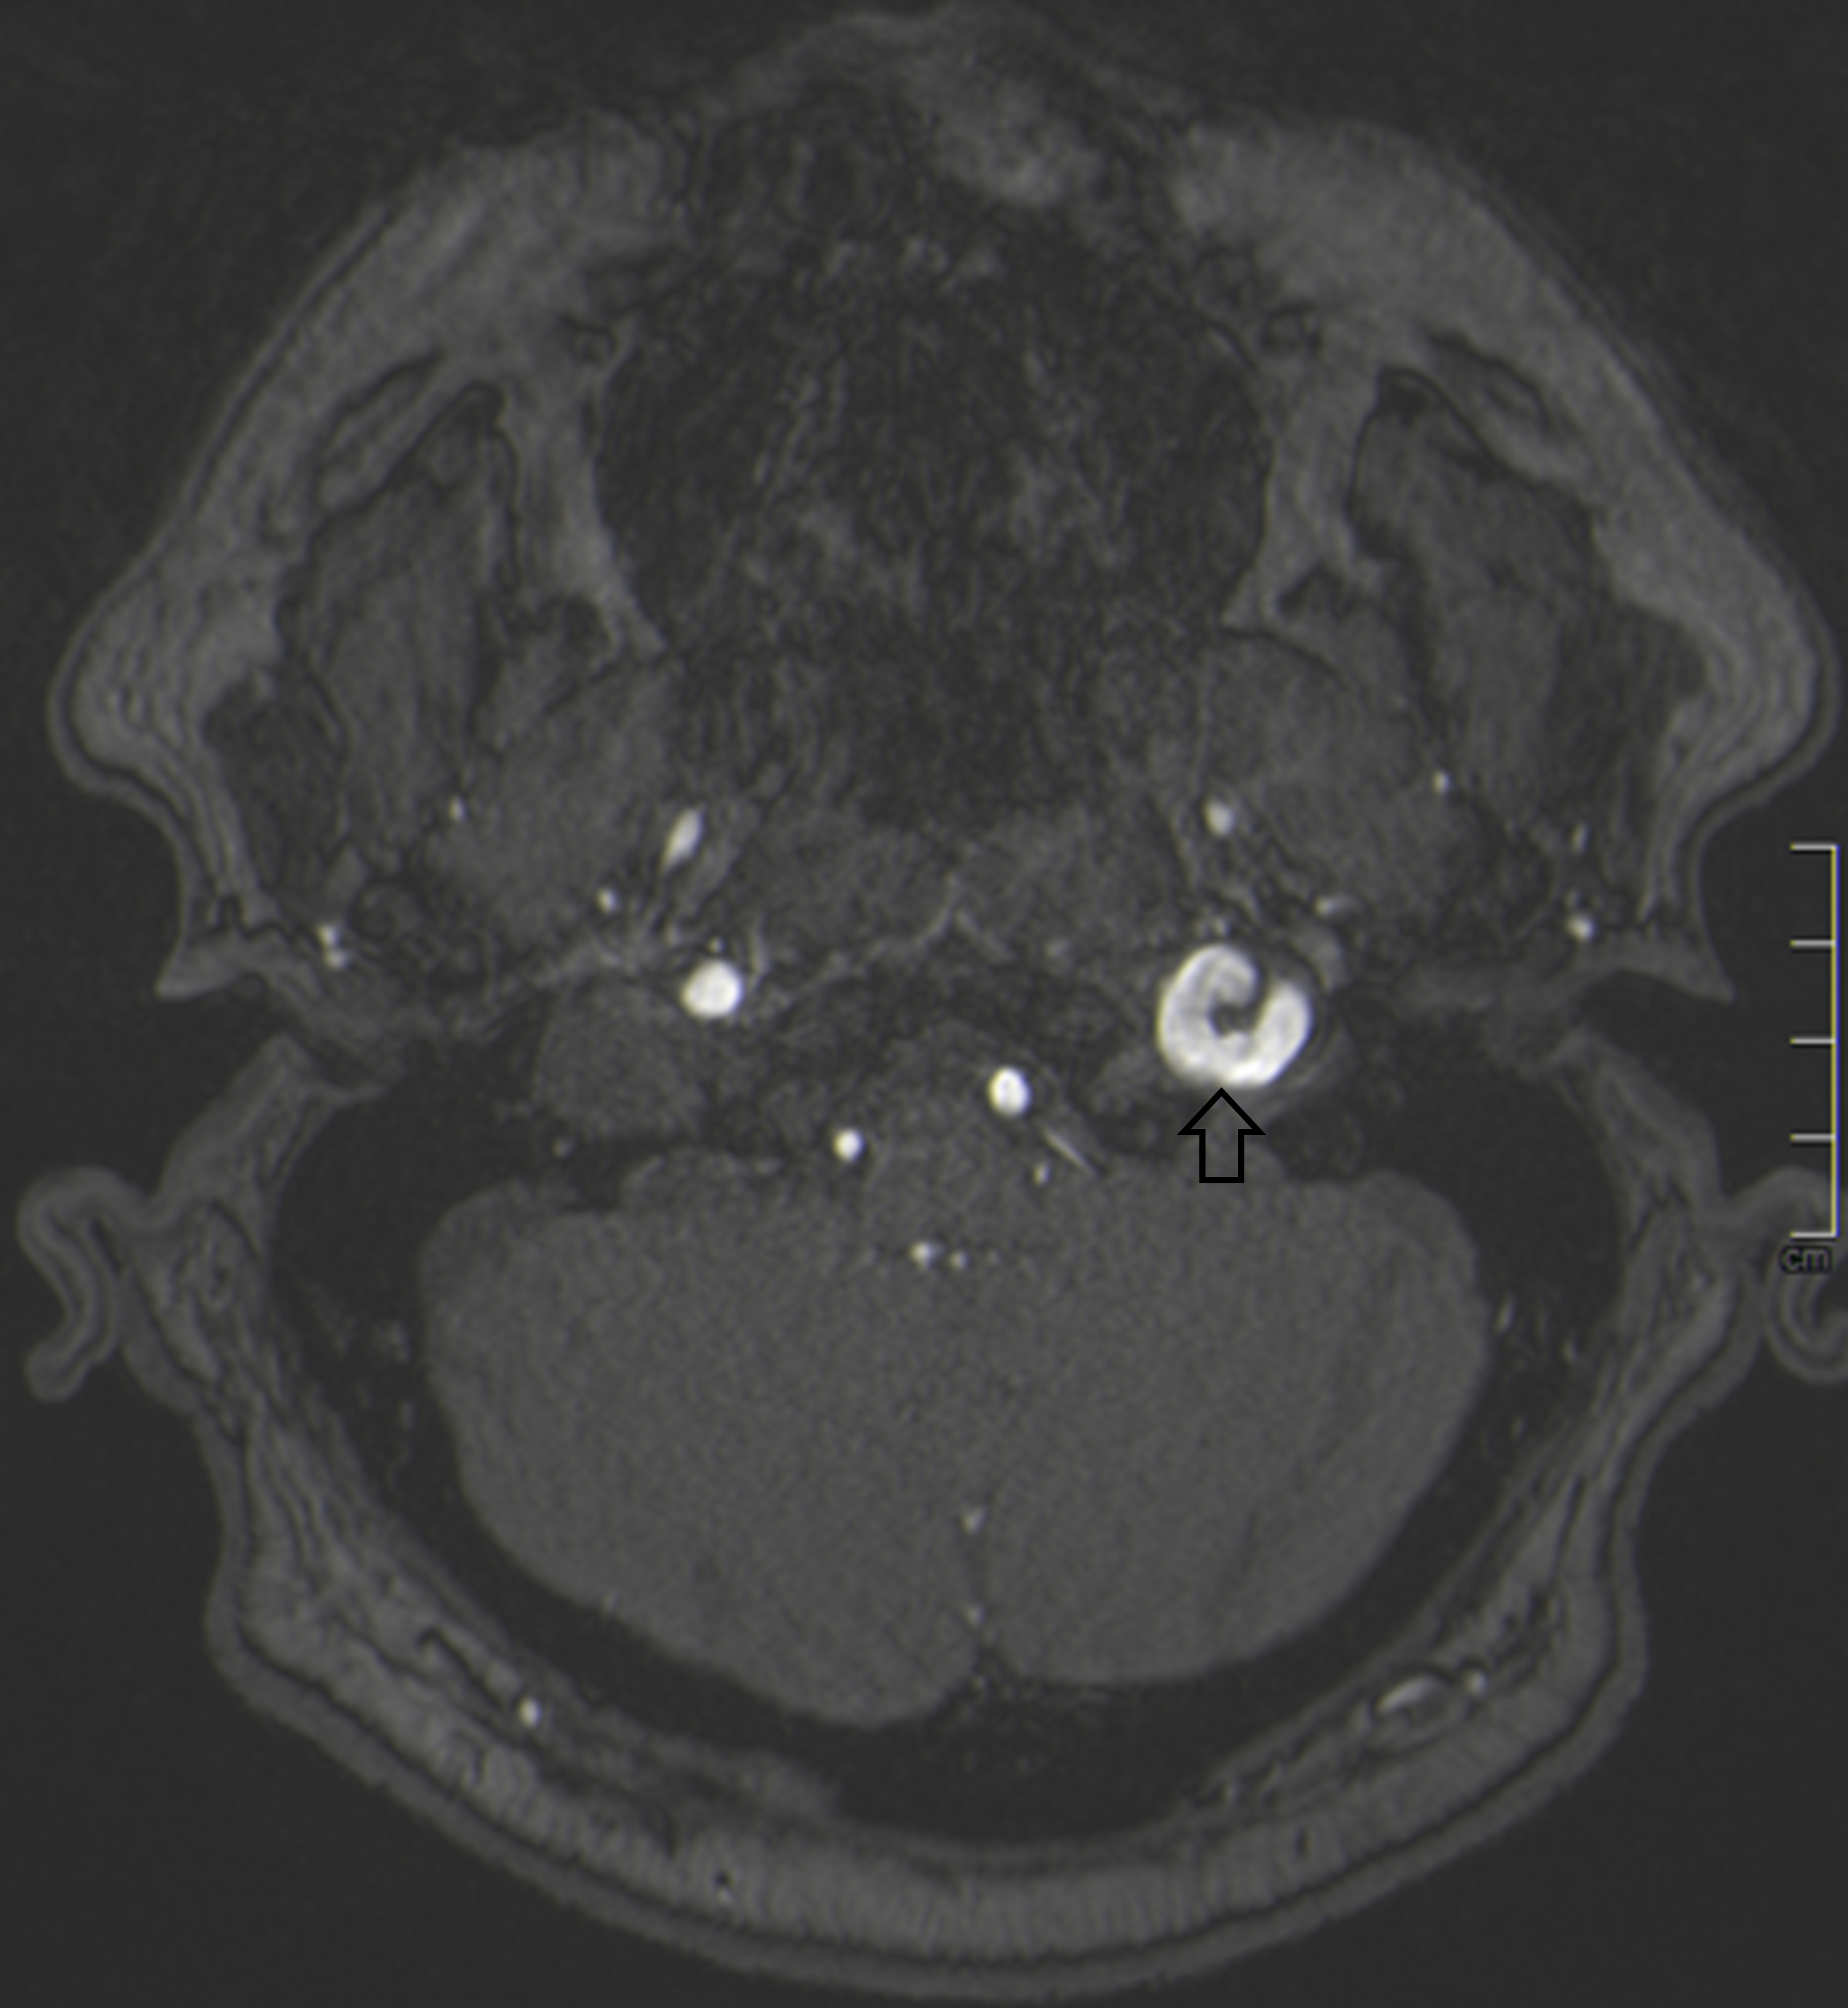

A 57-year-old male with rheumatoid arthritis, cervical spine …

Radiology Anatomy Images : Origin of the Hypoglossal nerve in MRI Anatomy

Cureus | Isolated Unilateral Hypoglossal Nerve Palsy Caused by Internal …